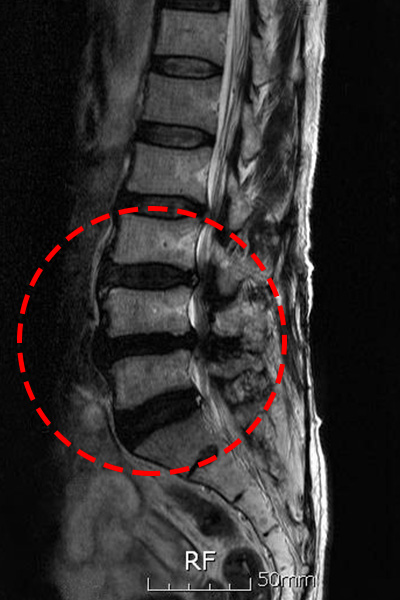

허리 디스크와는차이나게 척추관 협착증은 요통보다는 다리 저림이나 당김 증상이 있어, 보행에 제일 큰 고충을 체감할 수 있습니다. 때문에 오래 걷기가 힘들고 오래 걷지 않았음에도 자꾸 주저앉게 되는 성향이 존재하는데 표준적인 협착증의 증상이라 할 수 있습니다. 기본적으로 요추부(허리)의 문제이긴 하지만 허리디스크와 다르게 허리 통증이 한결같이 동반되지는 않으며, 있더라도 허리디스크에 대조해서 적은 정도의 통증이 일어납니다.

신경을 누를 때 신경의 지배를 받는 부위로 쑤시거나 화끈거리는 통증을 호소하게 되겠습니다. 만에 하나라도 경추부(목)에 척추관 협착증이 만들어 낸다면 상/하지 모두에 영향을 줄 수 있어 다리 근력감소, 보행 불편을 나타나게 할 수 있습니다. 요추(허리) 협착증은 방사통이 엉덩이에서 시작, 다리 아래로 하향할 수 있고 이 증상을 거의 좌골신경통이라 합니다.

척추관 협착증은 척추관의 좁아짐과 신경 구조에 압력이 가해지는 것으로 인해 많은 종류의 증상이 일어날 수 있어요. 주로 통증이 띄엄띄엄 생겨날며 허리, 목, 아니면 다리 등의 부위에서 통증이 나타날수 있습니다. 뿐 와 함께 또 저림 혹은 마비가 나타날수 있기도하고 특이하게다리에서의 저림이나 마비가 예사로 보여집니다.

또한 척추관 압력으로 인해 근육 약화가 발생하여 근력이 약해지는 경우도 있다고 합니다.

이로 인해 일상적인 움직임이나 운동에 괴로움을 겪어볼 수 있어요. 척추관 협착증으로 인해 척추 구조가 변형되었다거나 신경 구조에 압력이 적용되면 동작의 제한이 등장하고 허리 부위의 증상이 다리로 통증이 방사될 수도 있고요.

신경 압박이 안좋아지면, 신경을 통한 감각 전파이 순조롭지 않아 통증과 아울러 감각 저하, 이상감각을 호소할 수 있습니다. 경추 협착증의 경우, 감각 저하가 상 / 하지 모두 일어날 수 있습니다. 신경이 견딜 수 있는 수준 마지막으로 압력이 증가하면, 하지에 근력이 감량하게 되겠습니다.

심하다 못해 나중에는 족하수, 즉 발에 힘이 안입회하고 걸을 때 발이 끌리는 현상이 생기게 되겠습니다. 허리를 앞으로 숙이면, 척추관이 넓어지고 해서 허리를 숙이고 있거나 앉아있는 것이 소홀하게 느껴지고요. 허리를 펴고 오래 걷거나 서있기 어려우며 100~200m 이상 걸으면 다리에 힘이 빠지거나 통증이 심해 쪼그려 앉아서 쉬게 되겠습니다.